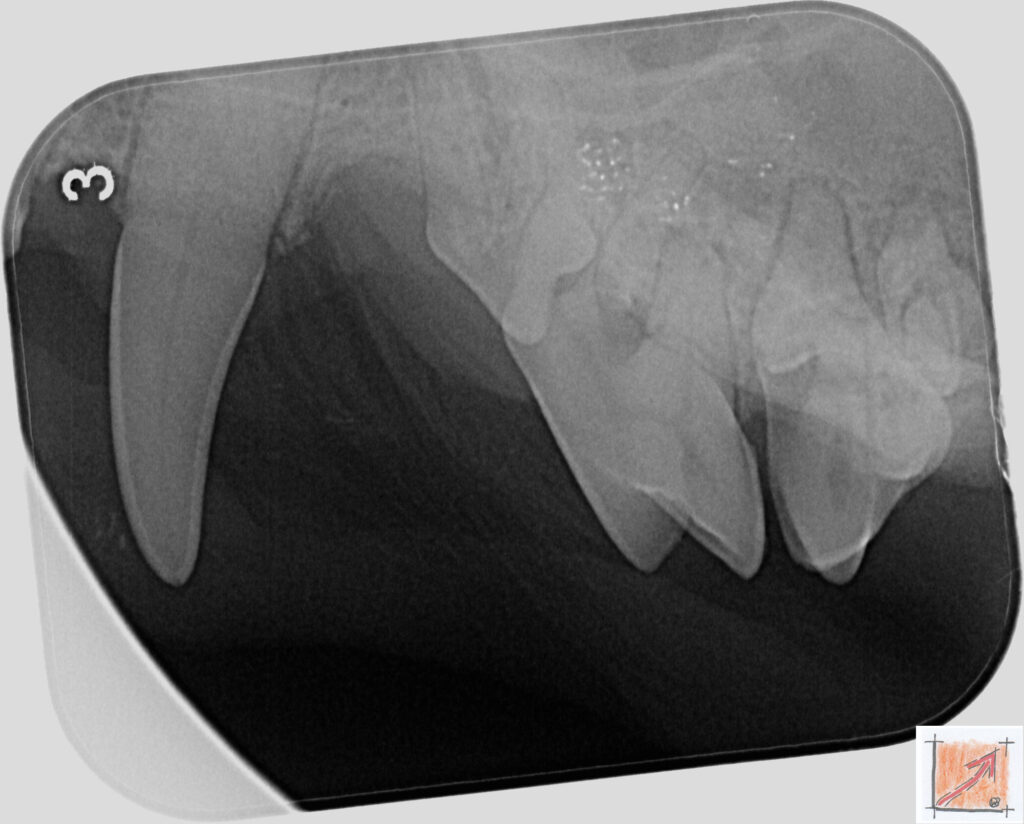

Röntgenbilder vom Thierrischen Orakel bei der Zahn-OP:

Warum Dentalröntgen beim Chihuahua lebenswichtig ist:

Ein Blick hinter die Kulissen von Chihuahua-Zähnen:

In dieser Galerie zeigen wir exklusive intraorale Röntgenaufnahmen einer Zahn-Operation beim Thierrischen Orakel als Chihuahua vom BauFachForum. Während oberflächlicher Zahnstein oft sichtbar ist, verbirgt sich die wahre Gefahr für das Herz meist unter dem Zahnfleischsaum.

Das digitale Dentalröntgen ist der Goldstandard in der modernen Tiermedizin, um parodontale Entzündungsherde und Wurzelabszesse sicher zu diagnostizieren. Für Chihuahuas wie dem Thierrischen Orakel, mit Mitralklappeninsuffizienz ist dieser diagnostische Schritt essenziell. Nur wenn versteckte Bakterienherde an der Zahnwurzel oder mit dem Fachbegriff Apikalabszesse erkannt und saniert werden, kann das Risiko einer bakteriellen Endokarditis oder einfach ausgedrückt einer Herzinnenhautentzündung minimiert werden.

Unsere Aufnahmen von Patienten dem Thierrischen Orakel verdeutlichen den Unterschied zwischen einer rein optischen Zahnreinigung und einer medizinisch fundierten Sanierung unter Röntgenkontrolle.

Chihuahua Mitralklappeninsuffizienz Trachealkollaps:

Wichtig ist im Vorfeld die Zahnhygiene des Chihuahuas. Die Bilder zeigen Dentale Röntgenbilder vom Thierrischen Orakel als Chihuahua-Hund während seiner Zahn-OP. Darstellung von Kieferknochen und Zahnwurzeln zur Diagnose von Parodontitis.

Zahnröntgenaufnahme bei Chihuahua Thierry:

Untersuchung der Zahnwurzeln auf Entzündungsherde als Prophylaxe gegen bakterielle Endokarditis.

Intraorales Dentalröntgen eines Chihuahuas:

Die Bilder zeigen Zähne und Wurzelstrukturen im Unterkiefer zur Planung einer Extraktion bei hochgradigem Zahnstein.